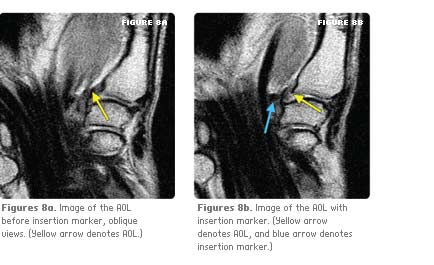

A standard MRI fiducial was sewn to the proximal and distal extent of the volar side of the AOL, soft tissues were replaced and the skin closed. Specimens were rescanned, to compare pre and post-dissection

ligament-labeled specimens.

Dissecting and tagging the ligament and repeating MRI confirmed the location of the AOL and validated the imaging technique.

Using the unique imaging protocol, the ligament was successfully identified in all cases. The open dissection and ligament tagging confirmed that what was visualized was indeed the structure of interest.